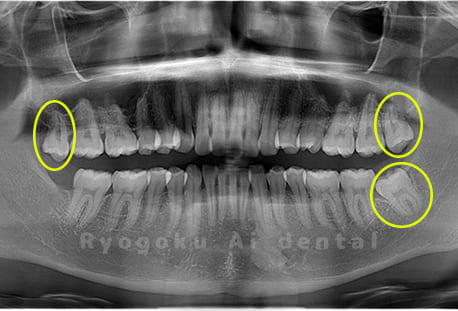

Case08

-

- 原因

- 下顎の水平埋伏智歯2本

- 治療内容

- 下顎の水平埋伏智歯2本を抜歯したケースです。

<リスク・副作用>

手術後は痛み、腫れ、痺れなどの副作用が生じる場合があります。